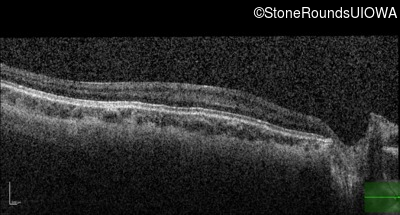

Optical Coherence Tomography - Left - 20/160 +1

Exemplar / OCT Stack

OCT Stack